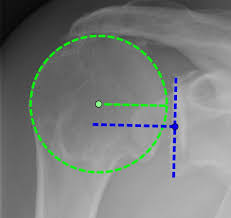

완전 파열이거나 비수술적 치료로 호전되지 않을 경우에는 수술이 필요합니다. 대부분 관절내시경을 이용한 봉합술이 시행됩니다. 절개 범위가 작아 회복이 빠르고 흉터가 적습니다.